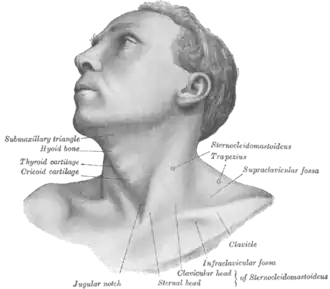

Anterolateral view of head and neck (supraclavicular fossa labeled at center right) | |